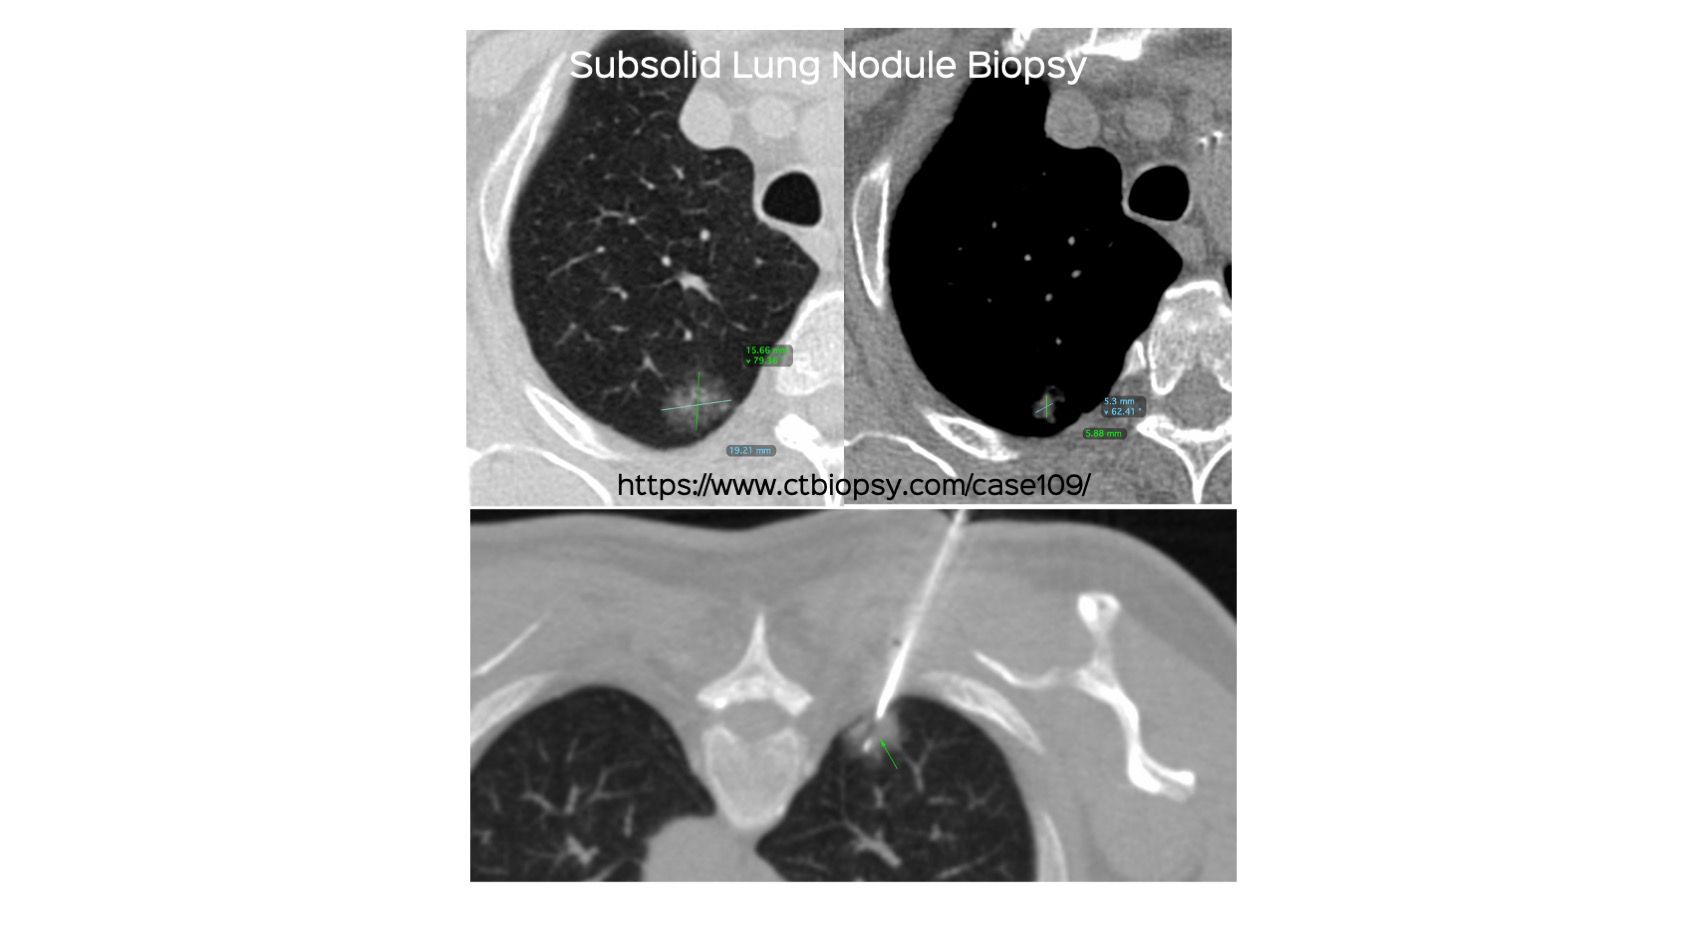

Case 109: Subsolid Lung Nodule Biopsy